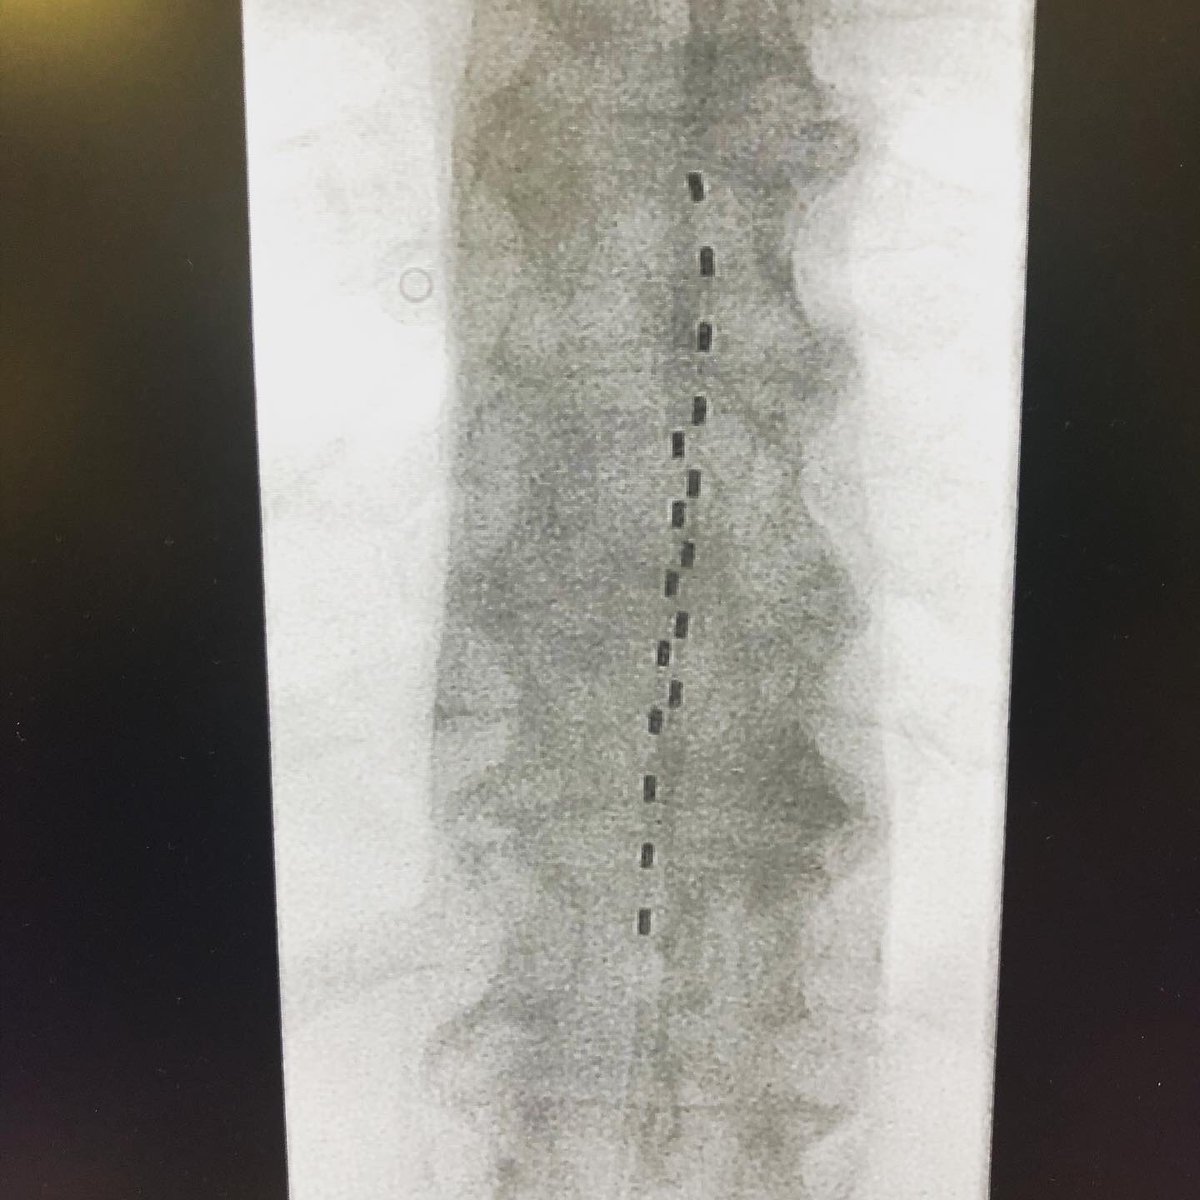

New challenge: difficult approach to the epidural space due to many vertebral cementations and L1 fracture that invades the spinal canal.

#spinalcordstimulation#chronicpain#lowbackpain#highfrequency@Nevro_HF10@primendocirugia@HMHOSPITALESpic.twitter.com/0ahELsyMhR